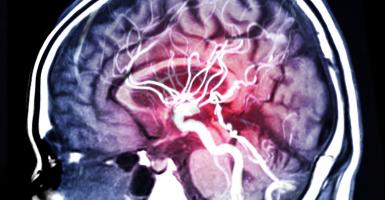

Les chercheurs de l'Université New Mexico Highlands (NMHU) constatent ici que l'impact du pied pendant la marche envoie des ondes de pression à travers les artères ce qui modifie de manière significative voire augmente l'apport de sang au cerveau. C'est une théorie nouvelle car jusqu'ici on pensait que l'approvisionnement en sang du cerveau ou flux sanguin cérébral était involontairement régulé par le corps et relativement peu affecté par les changements de pression sanguine associés à l'exercice ou à l'effort.

La marche, un exercice hémodynamisant : la marche produit des ondes de pression importantes dans le corps qui augmentent considérablement le flux sanguin vers le cerveau : l'impact du pied pendant la course entraine des ondes rétrogrades dans les artères qui se synchronisent avec la fréquence cardiaque et la vitesse de foulée pour réguler de manière dynamique le flux sanguin au cerveau. Ces constatations sont validées ici par échographie de l'artère carotide interne et mesure des diamètres artériels chez 12 jeunes adultes en bonne santé pendant le repos debout et durant la marche (à la vitesse d'1 mètre / seconde).

Un flux sanguin cérébral très dynamique : c'est la seconde conclusion de cette étude qui suggère que ce flux dépend directement des pressions aortiques cycliques qui interagissent avec les impulsions de pression rétrograde des impacts du pied. Et ce continuum d'effets hémodynamiques sur le flux sanguin du cerveau humain existe avec la marche, la course et dans une moindre mesure, le vélo : les effets de la marche sur le flux sanguin cérébral sont moins puissants que ceux causés par la course, mais plus importants que ceux associés au cyclisme.